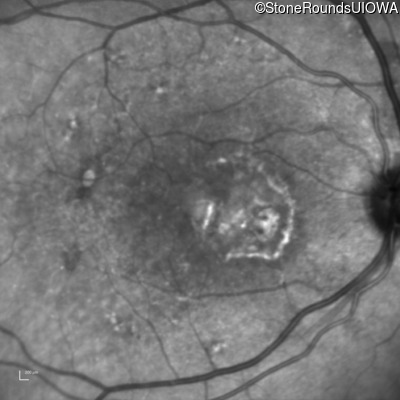

Fundus Photography - Right - 20/250

Exemplar

Infrared Fundus Photograph - Right - 20/250